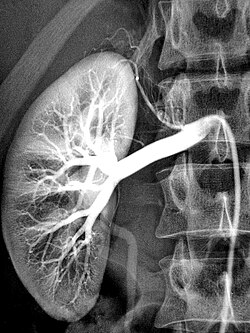

Die Wirkung von Kontrastmitteln besteht darin, das Signal, welches in der jeweiligen Untersuchung registriert wird, zu modifizieren. Ziel des Einsatzes ist, bei der Untersuchung Zusatzinformationen zu gewinnen. So kann man bei Röntgenaufnahmen Kontrastmittel verwenden, die Röntgenstrahlen stärker absorbieren als normales Weichteilgewebe. Gewöhnlich sieht man auf einem Röntgenbild beispielsweise keine Blutgefäße. Wenn man eine iodhaltige Lösung injiziert, werfen die Gefäße, in die die Lösung gelangt, Röntgenschatten und werden so sichtbar (Angiografie).

Iodhaltige Kontrastmittel sind wasserlösliche Substanzen, die entweder intravaskulär gespritzt oder direkt in das darzustellende Gewebe/Hohlorgan injiziert werden. Sie werden zu über 90 %

über die Nieren ausgeschieden. Sie dienen zur Darstellung der Nieren und Harnwege

(Urografie/Ausscheidungsurografie), der

Venen (Phlebografie), der Arterien

(Arteriografie) oder anderer Organe. Die verschiedenen iodhaltigen

Kontrastmittel unterscheiden sich vor allem in den Trägermolekülen, in der Zahl der pro Trägermolekül gebundenen Iodatome (1 bis 6) und in ihren physiko-chemischen

Eigenschaften (Osmolalität, Viskosität, Hydrophilie).